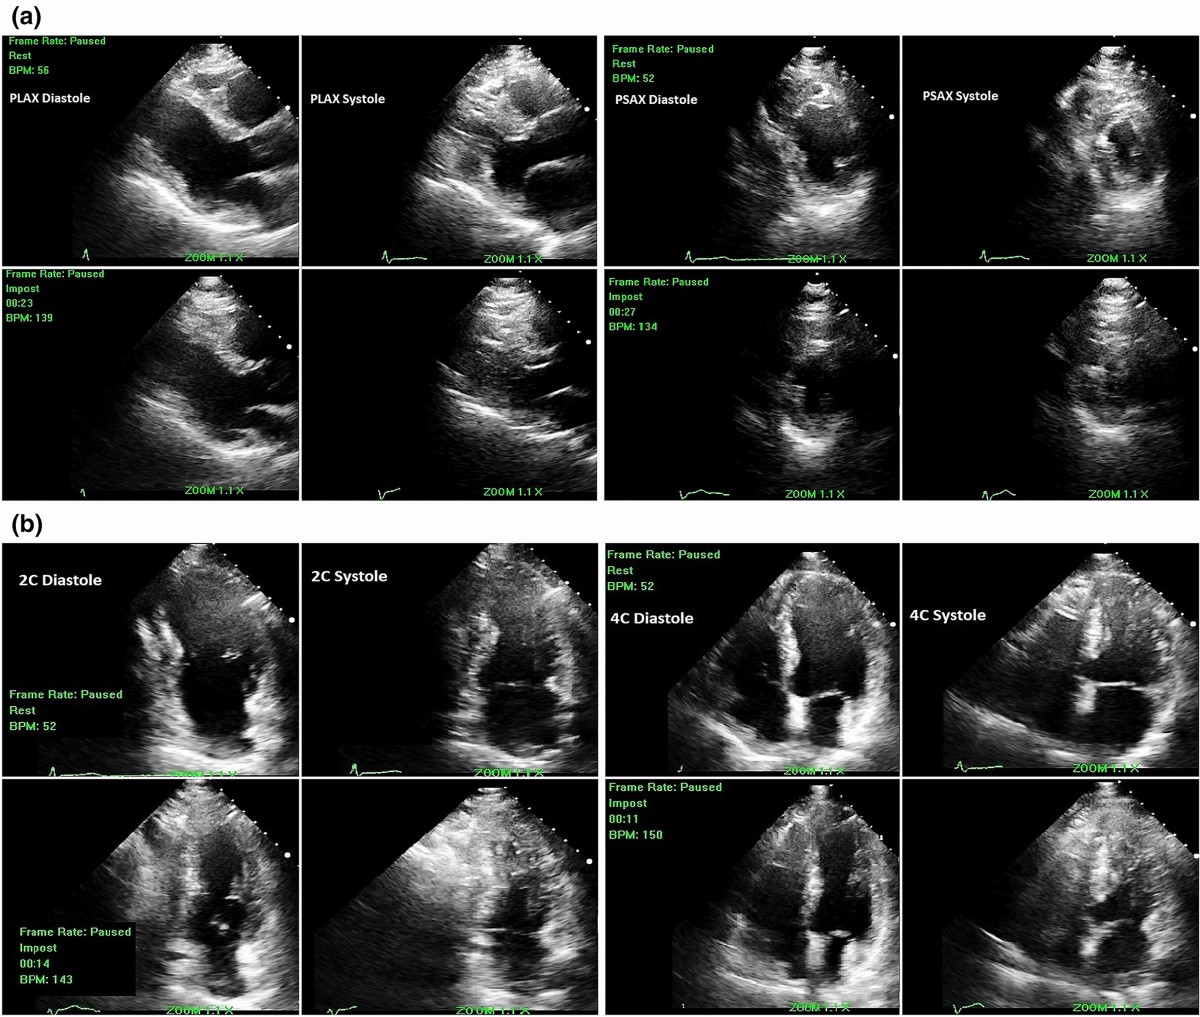

» Interpreting stress echo (99) 사진

Interpreting stress echo (99) 사진